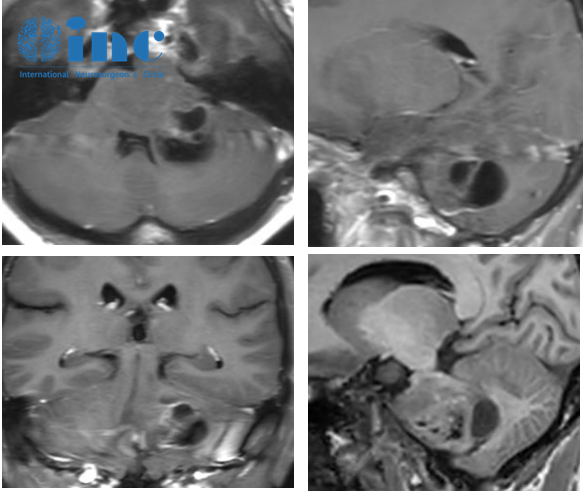

腦干彌漫中線膠質(zhì)瘤案例圖

吳女士術(shù)前(紅色)術(shù)后(藍(lán)色)MRI對(duì)比

術(shù)后2天:CT影像示正常術(shù)后表現(xiàn),病人被轉(zhuǎn)回神經(jīng)外科病房。她在康復(fù)治療師的指導(dǎo)下開始緩慢活動(dòng)。住院期間,復(fù)視和面神經(jīng)麻痹持續(xù)存在,但有所好轉(zhuǎn)。步態(tài)在術(shù)后期間得到穩(wěn)定。核磁檢查證明該內(nèi)生型腫瘤得到了大約90%的切除。